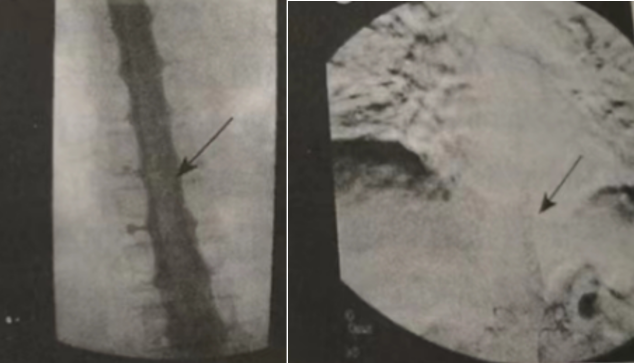

10)脊髓动脉造影(图2):左侧T12供应的异常迂曲血管,符合硬脊膜动静脉瘘。超选择进入左侧T12肋下动脉行NBCA栓塞术,术后痿及引流静脉未见显影。

图2 脊髓造影可见脊髓表面的蚯蚓状充盈缺损;动脉造影证实了硬脊膜动静脉瘘的存在[1]